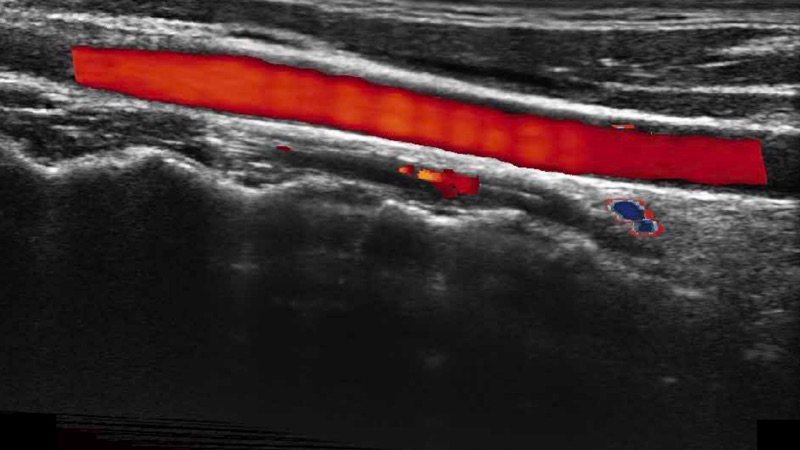

高分辨率血流成像技術提高了對低速血流信號的檢測能力。在提高空間分辨率的同時,也克服了血流外溢現象,為用戶提供更加真實的血流動力學信息。

通過色彩血流和實時寬景相結合,可觀察到完整的靜脈或動脈的血流,方便醫(yī)生檢查。實時掃查過程中,如有任何操作失誤也可以很容易地進行回掃擦除,而不會中斷掃查。